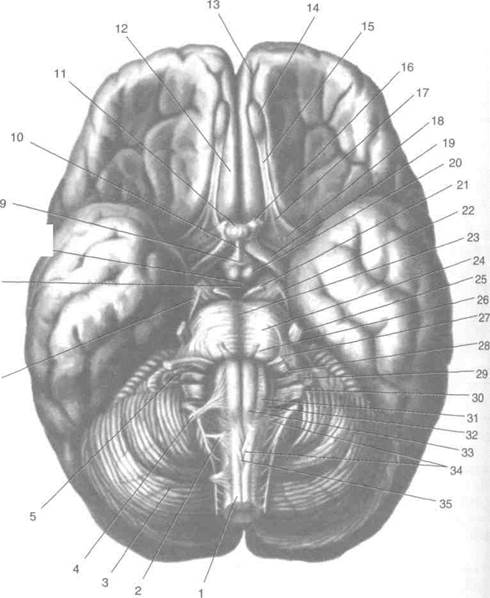

Необычные объекты: Переднее продырявленное вещество

Раздел: Альбом открытий